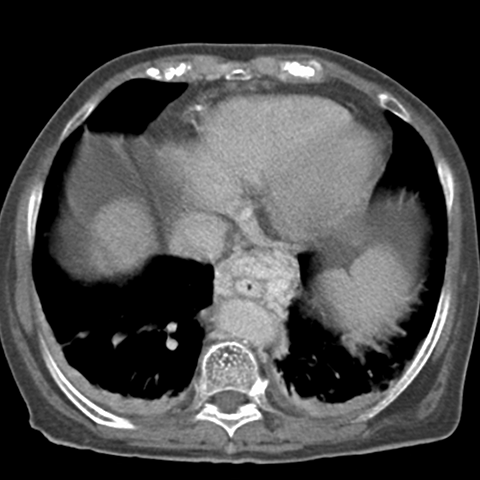

Cirrhosis and Portal Hypertension, CT ( axial ) [1 of 3]